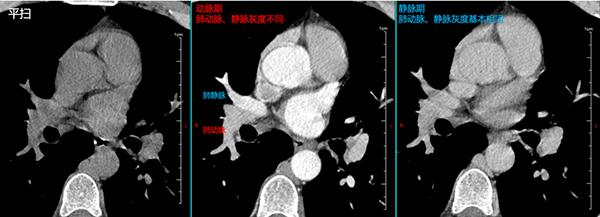

增强后,右肺叶间的淋巴结与肺动脉界限非常清晰。

进行增强CT扫描的同时会缓慢注射碘造影剂,根据注射造影剂后CT扫描的时间间隔,分为静脉期、动脉期,腹部增强CT还有门脉期、延时期。胸部增强CT动脉期一般会用C+A表示,这时肺动脉CT值较高,与周围病变区别非常明显,但由于造影剂进入人体内时间较短,血管内灰度可能不均匀。静脉期一般会用C+V表示,此时肺动脉静脉均有造影剂经过,灰度比较均匀,但与软组织(淋巴结、病灶)对比度较动脉期略低。